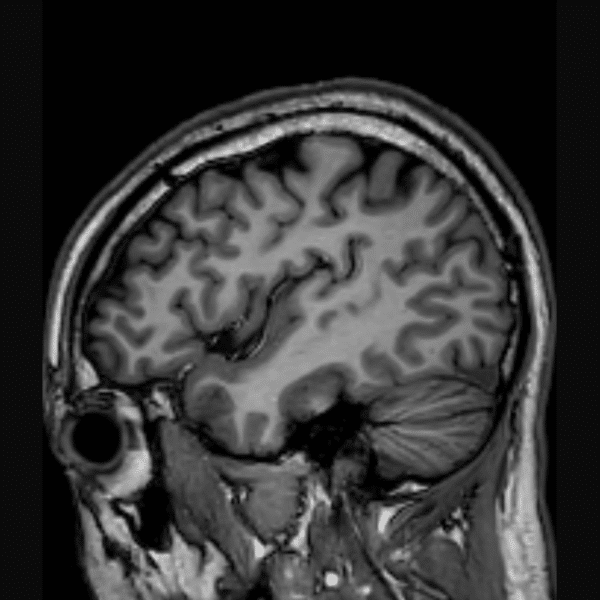

Brain 3D T1WI

3.0T Philips Ingenia CX

3D TFE

(L) 1.0×1.0x1.0 mm

(R) 0.8×1.1×1.1 mm

Conventional SwiftMR™ 03:14 02:07 (35% Faster)